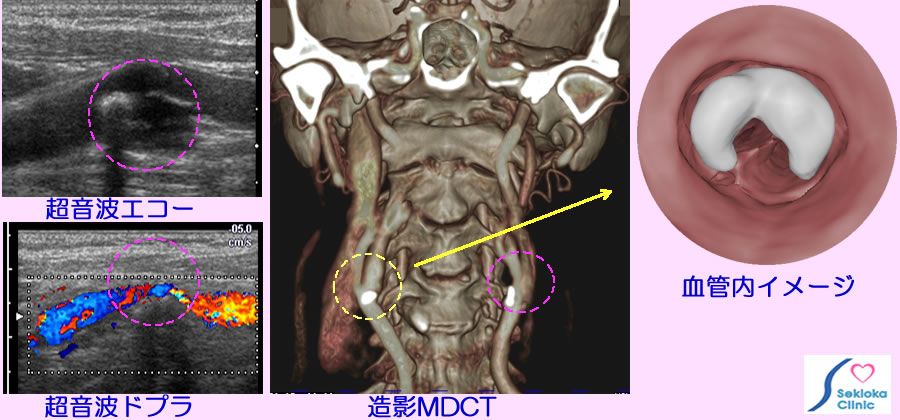

| 診断 | 超音波エコーは簡便で容易な検査、血管を詳細、広範囲に検査するにはMDCT、MRI。添付画像の波線円内が頸動脈の狭窄部位。左上段の超音波エコーで動脈硬化病変(アテローム)と血管狭窄を認め、左下段はドプラ法で血管内の血流を画像化。中央の画像は造影MDCT 波線円内の狭窄部位に白く描画されているのは石灰化(動脈硬化)病変です。黄色波線内の血管内イメージを3次元MDCT画像から作成した画像を右側に示しています。白く描出された石灰化病変で血管内腔は狭くなり、その奥に内・外頸動脈の分岐部が見えます。容易かつ明瞭に血管内の状態を理解できます。 |